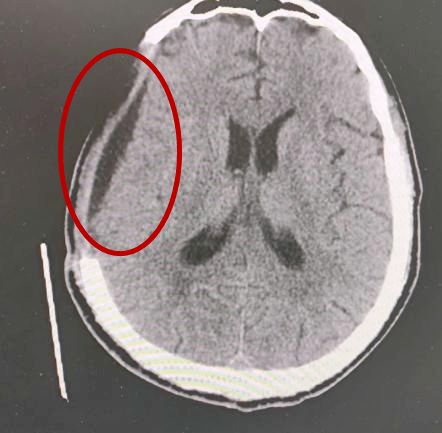

硬膜下积液影像学表现